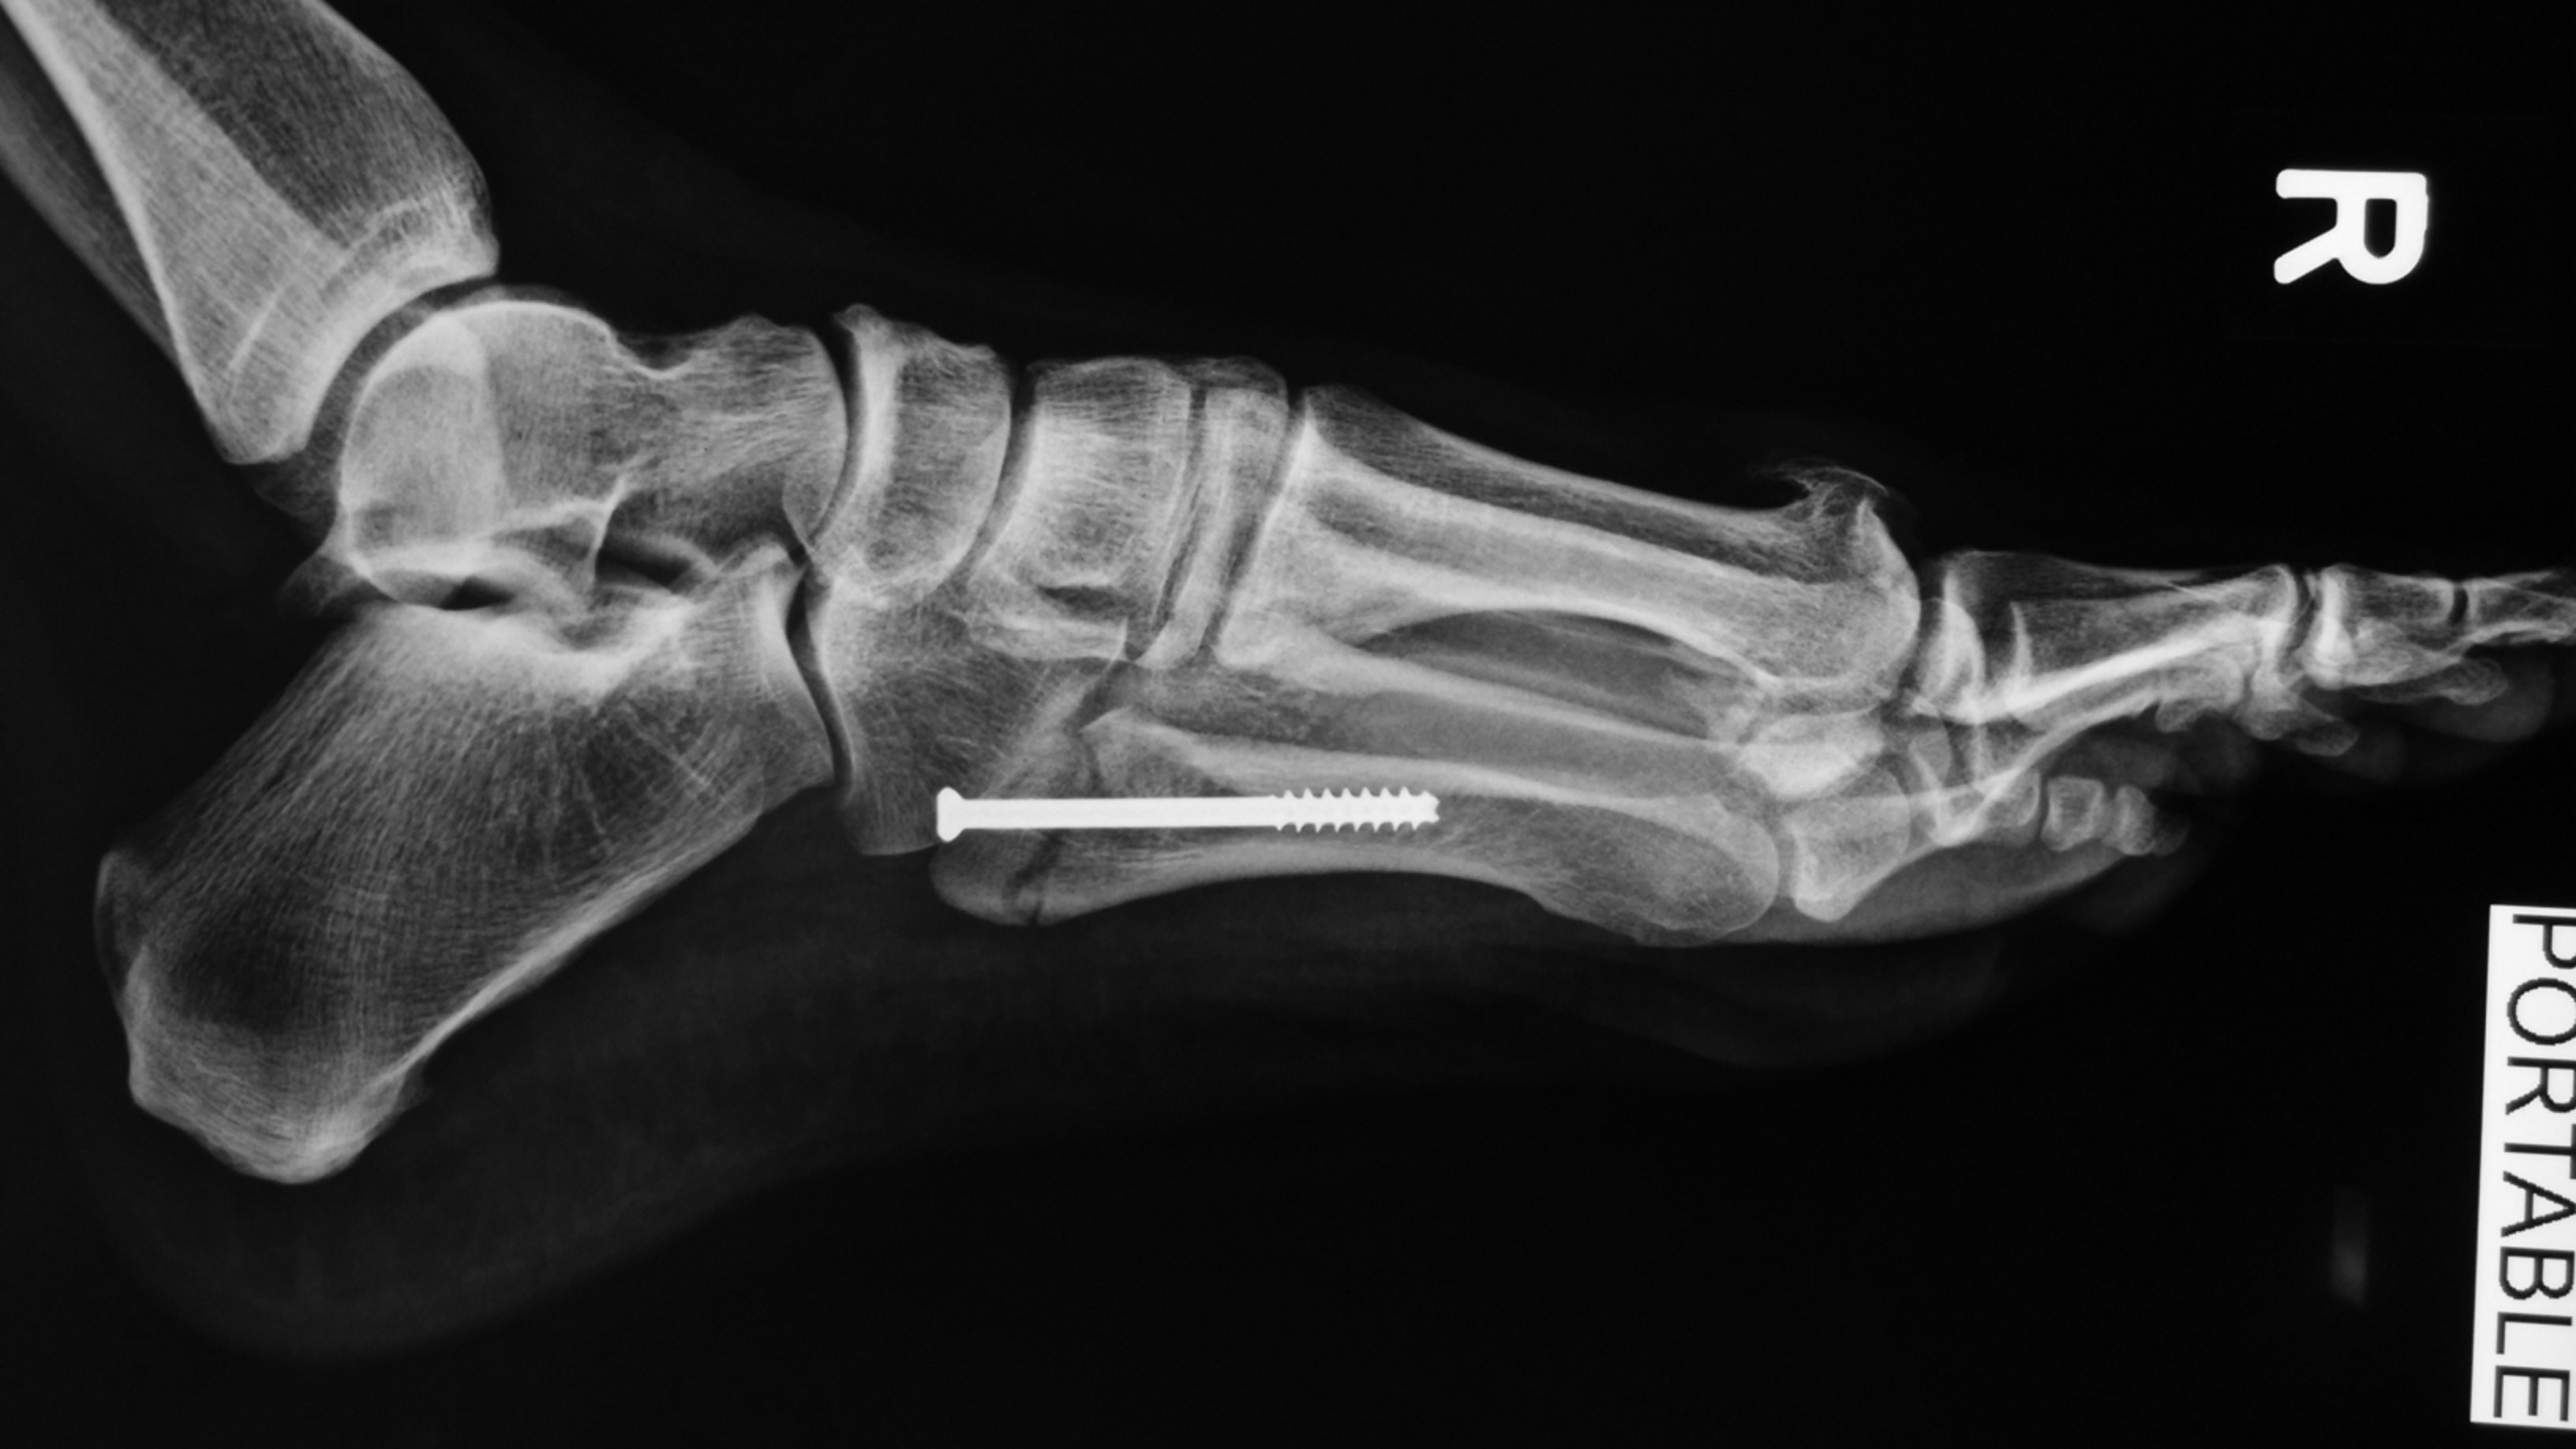

This is a case of a displaced avulsion fracture of the 5th metatarsal styloid. It is also sometimes referred to as the “Pseudo-Jone’s fracture”.

Percutaneous cannulated screw fixation of this displaced avulsion fracture of the 5th metatarsal base was performed.

This procedure is done via a small incision and guided by x-rays fluroscopy.

This is the final result: